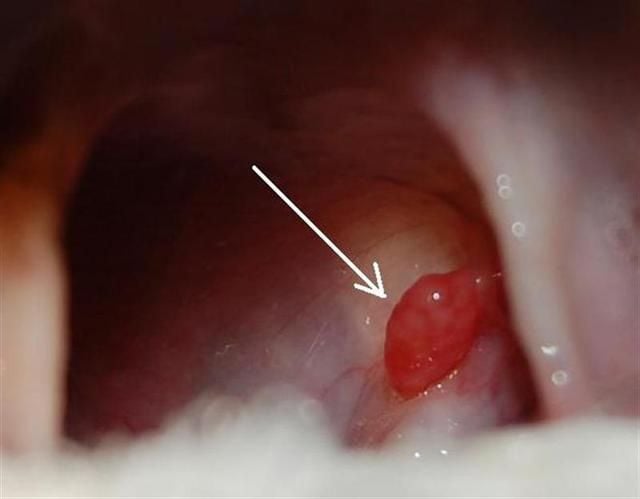

A garat, a mandulákkal, a szájüreget köti össze a nyelőcsővel. Köhögés, öklendezés, nyelési nehézségek és fájdalom okozta étvágytalanság a garat betegségeinek jellegzetes tünetei. Mandulagyulladás és a nyirokcsomók duzzanatai esetén általában a testhőmérséklet is megemelkedik. A garat betegségei többnyire a gégére is átterjednek. A garatot a szájon át bevilágítva megtekintéssel, kívülről tapintással, szükség esetén röntgenátvilágítással vizsgáljuk. A garat gyulladását a nyálkahártya és a mandulák kipirosodása, duzzanata jelzi; általános fertőzések: szopornyica, fertőző májgyulladás stb. okozhatják. A betegség kezdeti szakaszában a beteg minden esetben lázas. Bizonytalan diagnózis esetén vizelet- és vérvizsgálattal juthatunk további információkhoz. A garat nyálkahártyájának helyi izgalmát okozhatja hó evést követő megfázás, idegen test (tű, drót, csontszilánk, faszálka) vagy helyi fertőzés. A kutya gyakran öklendezik, elülső lábaival a nyakát és a fejét kaparja vagy a földhöz, szőnyeghez dörzsöli a fejét. A gyógyulás előfeltétele a háttérben meghúzódó általános fertőző betegség felszámolása. Az idegen testeket altatásban, megfelelő fogóval lehet eltávolítani, a garatot pedig fájdalomcsillapító, duzzadást csökkentő vagy helyi érzéstelenítő szerekkel kell kezelni; az esetleges sérüléseket antibiotikumokkal ecseteljük. Lelettől függően görcsoldó és köhögéscsillapító injekciókkal együtt is adhatóak a fenti gyógyszerek. Ha a gyulladás okozta duzzanat gátolja a légvételt, akkor kortizon adása is szükséges. Heveny mandulagyulladás legtöbbször fiatal kutyáknál alakul ki. Ha nem sikerül teljes mértékben meggyógyítani a fertőzést, a folyamat idültté válhat. Különösen kis testű fajtáknál gyakori a mandulagyulladás. Nem feledkezhetünk meg azonban arról, hogy e fajtáknak eredendően nagyobbak is a mandulái. A kezelést antibiotikumokkal vagy szulfonamidokkal és fájdalomcsillapító szerekkel végzik, és a meleg gyapjúsál is jótékony hatású.